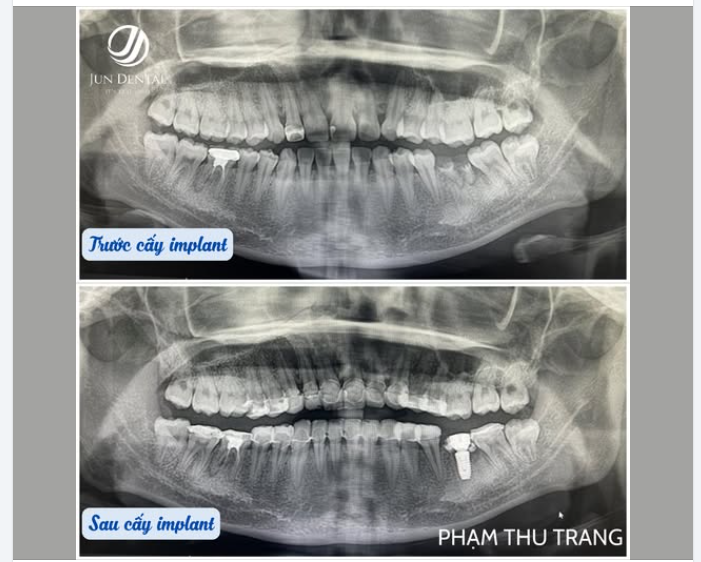

CẤY IMPLANT KHÔNG SƯNG – KHÔNG ĐAU – KHÔNG CẦN NGHỈ DƯỠNG